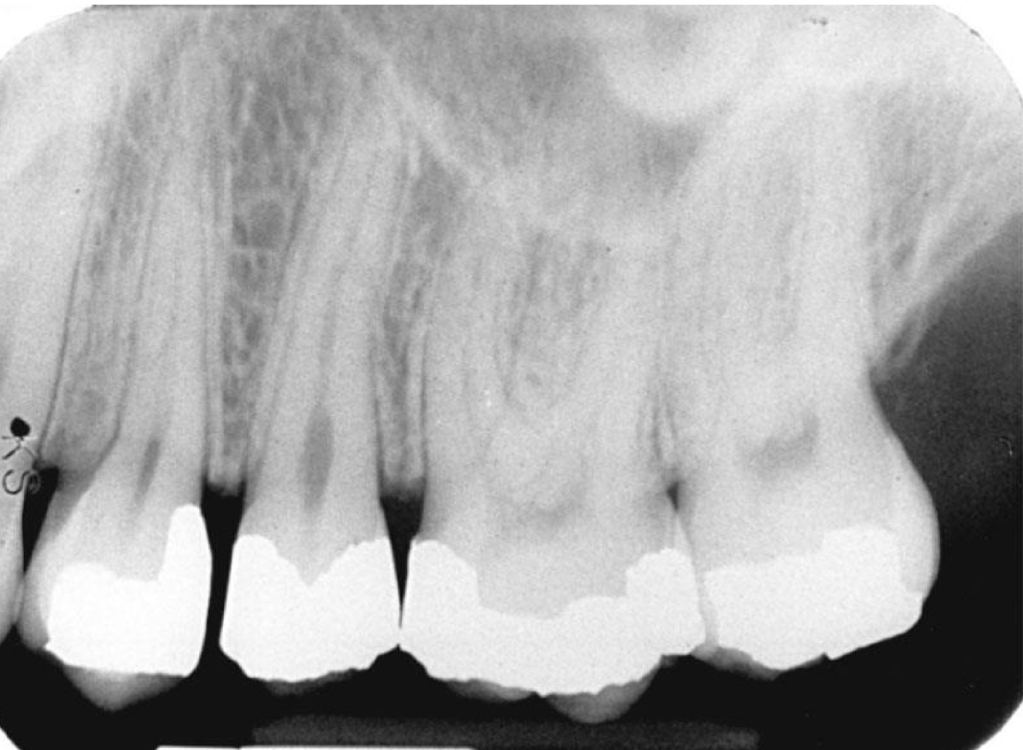

Periodontal disease

Group of diseases that affect supporting structures ranging from inflammation of gingiva to destruction of supporting bone and PDL

Radiographic examination tells

Pattern, distribution , and severity of bone loss

Bone loss

Difference between the physiologic bone level and height of remaining bone

Pattern of bone loss

Horizontal vs vertical

Severity of bone loss

Slight, moderate , severe

Local irritants may contribute to: calc, defective restorations

Defective amalgam